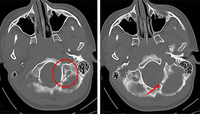

Fracture of temporal bone

From the teaching collection of Demetrios Demetriades; used with permission